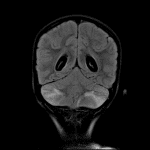

- MRI

- Patchy T2/FLAIR hyperintensity involving gray and white matter in both cerebellar hemispheres with associated cerebellar swelling and partial effacement of the fourth ventricle

- Descent of the bilateral cerebellar tonsils into the foramen magnum with mass effect on the upper cervical spinal cord

- Enlargement of the lateral and third ventricles with periventricular T2/FLAIR hyperintensity

- Thin diffuse pial enhancement along the surface of the cerebellum

- No evidence of acute infarct or hemorrhage